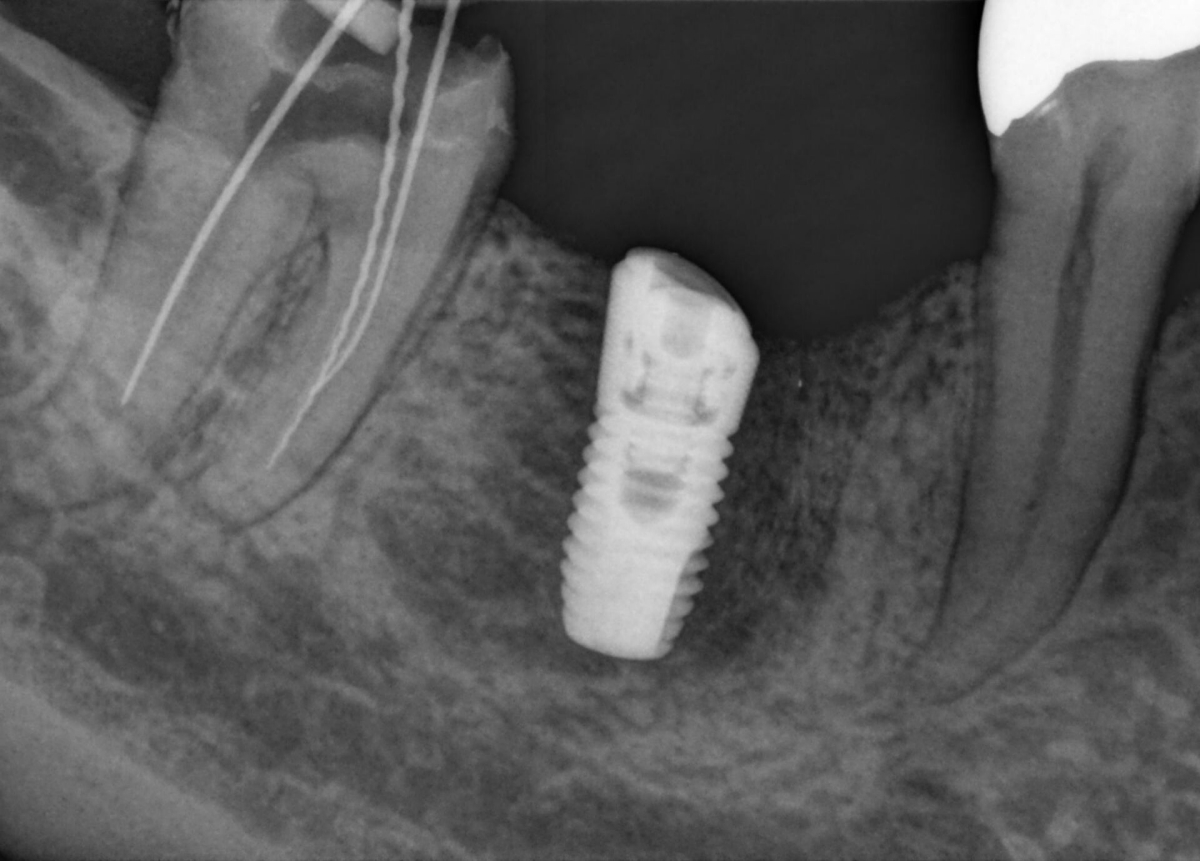

MARS

In MARS worden metaalartefacten op 3D-beelden automatisch gedetecteerd en gereduceerd met behulp van innovatieve algoritme.

MARS – software voor reductie van metaalartefacten

Metaalartefacten vormen een uitdaging bij het bewerken van 3D-röntgenbeelden. Tijdens de driedemensionale reconstructie leiden radiopake objecten tot schaduw- en streepvorming, wat de resultaten kan beïnvloeden. Met MARS worden metaalartefacten automatisch gereduceerd en wordt de diagnostiek vergemakkelijkt.

We hebben MARS uitgetest en zijn er zeer enthousiast over. We zien nu zo veel meer dat we ons niet meer kunnen voorstellen MARS niet te gebruiken.